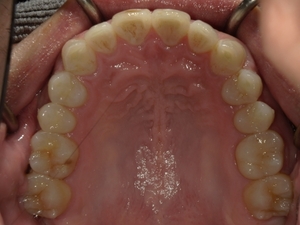

ガタガタとした歯並びや八重歯(叢生)CASE74